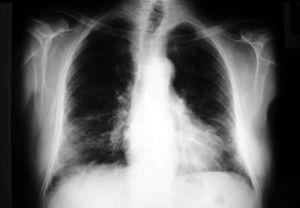

Se trata de un paciente de 75 años que el año anterior fue diagnosticado de carcinoma vesical en estadio I, al que se le practicó resección transuretral y fue tratado con instilaciones intravesicales de BCG. No se realizó profilaxis antituberculosa previa al tratamiento con BCG intravesical. El paciente recibió la última instilación dos semanas antes del ingreso; desde entonces presentó episodios de fiebre y escalofríos, motivo por el que fue tratado en otro hospital empíricamente con ciprofloxacino por sospecha de infección urinaria y con isoniacida debido al antecedente del tratamiento con BCG. A los tres días de ser dado de alta consultó de nuevo por fiebre, escalofríos y disnea progresiva. Ingresó en la Unidad de Cuidados Intensivos (UCI) de nuestro hospital por insuficiencia respiratoria aguda. La temperatura axilar era de 37,5º C, el pulso 65 x´, la presión arterial de 135-55 mmHg y la frecuencia respiratoria de 24 x´. En la exploración física destacaban crepitantes en ambas bases pulmonares y hepatomegalia de dos traveses. El sedimento de orina no fue patológico. La analítica mostraba un hematocrito, leucocitos y plaquetas normales, bilirrubina total normal, GPT 203 U/l, GOT 165 U/l, fosfatasa alcalina 249 U/l, GGT 148 U/l y LDH 1026 U/l, con el resto de parámetros bioquímicos normales. La GSA con FiO2 al 50%: pH 7,48, pO2 63 mmHg, pCO2 27,6 mmHg, HCO3 20,9 mmol/l, exceso de base -0,5 mmol/l, saturación arterial de O2 93,7%. En la radiografía de tórax se apreciaba un patrón miliar intersticial (fig. 1).

Figura 1. Radiografía de tórax donde se observa un patrón miliar.